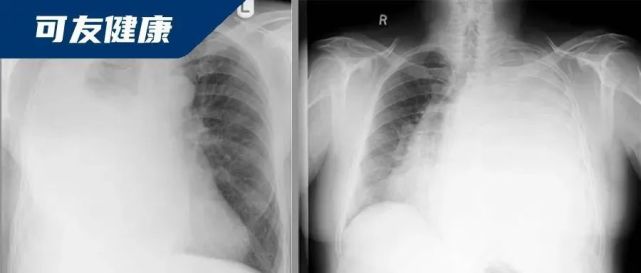

3.  肺不张

还有一种情况,就是肺泡不能充分的充气。大家可以想象一下,如果一个气球的吹气口被堵牢了,气球就吹不起来了,所以这时候整个肺组织会塌陷,也表现为白肺的情况。这种情况,比如肿瘤压迫,有些痰栓也会引起,这时候有经验的影像科医生或者临床医生可以鉴别出来。

图片

肺不张